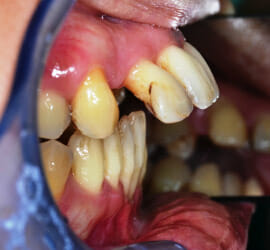

Paziente di 35 anni affetta da parodontite aggressiva generalizzata e da osteoporosi.

La paziente presentava anche un problema di spostamento evidente dei denti dell’arcata superiore, per cui necessitava di terapia ortodontica.

La paziente è stata quindi sottoposta a sedute di terapia parodontale microinvasiva eseguita con microscopio operatorio e laser.